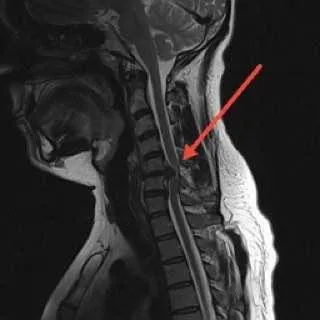

Специалисты Истринской больницы провели 42-летнему пациенту уникальную операцию на позвоночнике. У мужчины ранее обнаружили опасную грыжу.

Пациент жаловался на нарастающую слабость в ногах и сильные боли. Его осмотрел невролог, который назначил проведение МРТ. По результатам исследований мужчину передали в руки нейрохирургов.

«Причиной этих симптомов стала огромная секвестрированная грыжа поясничного отдела позвоночника, которая практически полностью перекрывала весь спинномозговой канал и сдавливала нервные корешки», — рассказал нейрохирург Николай Карпов.

Пациенту потребовалась операция, во время которой специалисты провели микродекомпрессию, а также удалили разрушенную часть диска.

«Если бы мы не оперировали пациента и оставили все как есть, этот секвестр продолжал бы сдавливать нервные корешки, и в итоге пациент потерял бы возможность ходить», — пояснил врач.

Вмешательство, требовавшее ювелирной точности, длилось около часа. Уже через сутки мужчина смог встать и начал передвигаться под контролем специалистов.

Позже пациента выписали. Двигательные функции полностью восстановились, поэтому реабилитация ему не требуется.